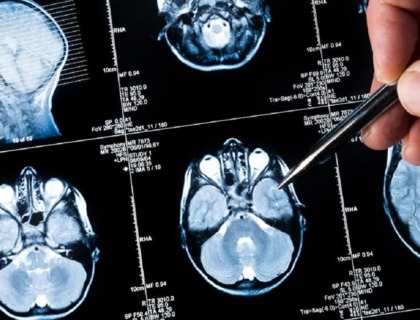

El síndrome de Duane afecta los músculos que controlan el movimiento del ojo. En todos los casos, una persona con síndrome de Duane tendrá poca o ninguna capacidad para mirar hacia afuera (hacia sus oídos) y, a menudo, tendrá una capacidad limitada para mirar hacia adentro (hacia su nariz).

La cirugía puede ser una opción para el síndrome de Duane, pero a menudo esto no es posible.